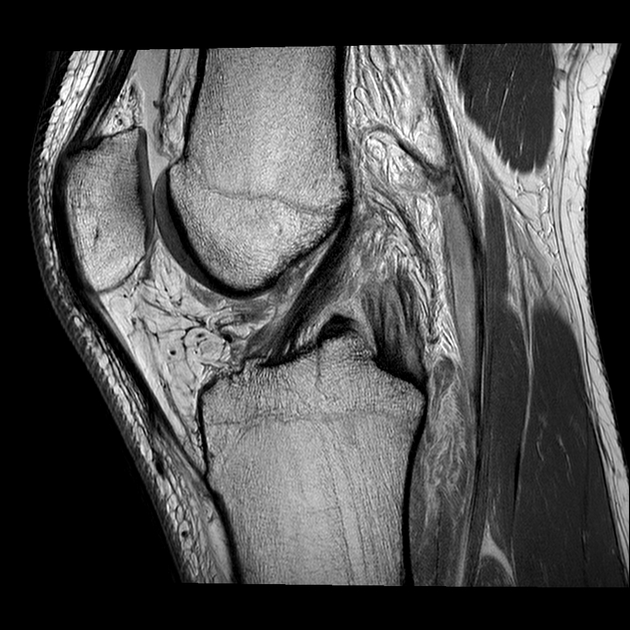

- Rezonanța magnetică (IRM/MRI) – Oferă imagini detaliate ale țesuturilor moi, inclusiv ale ligamentului LIP . Pot exista însă cazuri în care imaginile apar normale, mai ales dacă leziunea s-a produs cu mai mult de 3 luni în urmă.